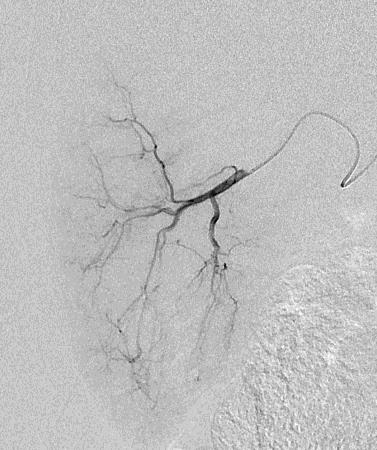

Can we predict local response? Uptake of CM/MP(造影剂/微球的吸收)

Uptake of contrast day +1

Uptake grade 3 (HepaSphere 50mg, Irinotecan 200mg)

Uptake grade 0-1

Uptake predicts local response(HepaSphere™ 100 mg,Irinotecan 400 mg)